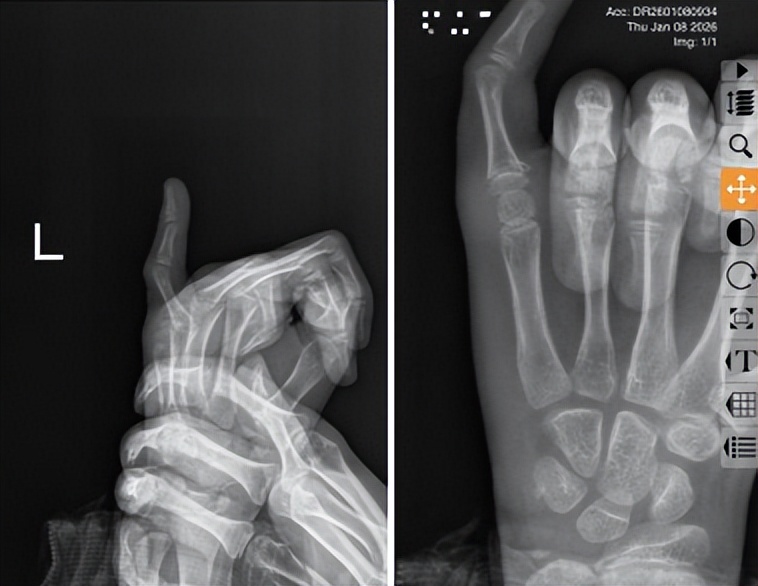

手法复位室的薛安邦主治医师第一时间对小兰进行查体,左手指明显肿胀、畸形,初步判断为儿童指骨骨折的典型表现。随即安排X光检查,影像结果显示,左手第五指骨近节指骨基底粉碎性骨折,伴有骨折端移位及成角畸形。

考虑到小兰年仅8岁,骨骼还处于发育阶段,手术治疗可能会影响后续生长,建议优先尝试手法复位治疗。经与家属充分沟通并取得知情同意后,在科室主任董博的指导下,薛安邦医师制定了周密的治疗方案。董博主任强调:“该骨折部位邻近骨骺,操作时须在充分牵引下纠正移位,避免对骨骺的过度的刺激。”同时向家属表示:“通过精准的手法复位,有望实现功能恢复与外观重建的双重目标。”

术后复查X光片显示,骨折断端对位对线良好,达到理想复位标准。看到女儿疼痛缓解、手指恢复自然姿态,家长悬着的心终于放下,连连致谢:“多亏了你们的专业治疗,不然我们真不知该如何是好,太感谢红会医院的医生了!”